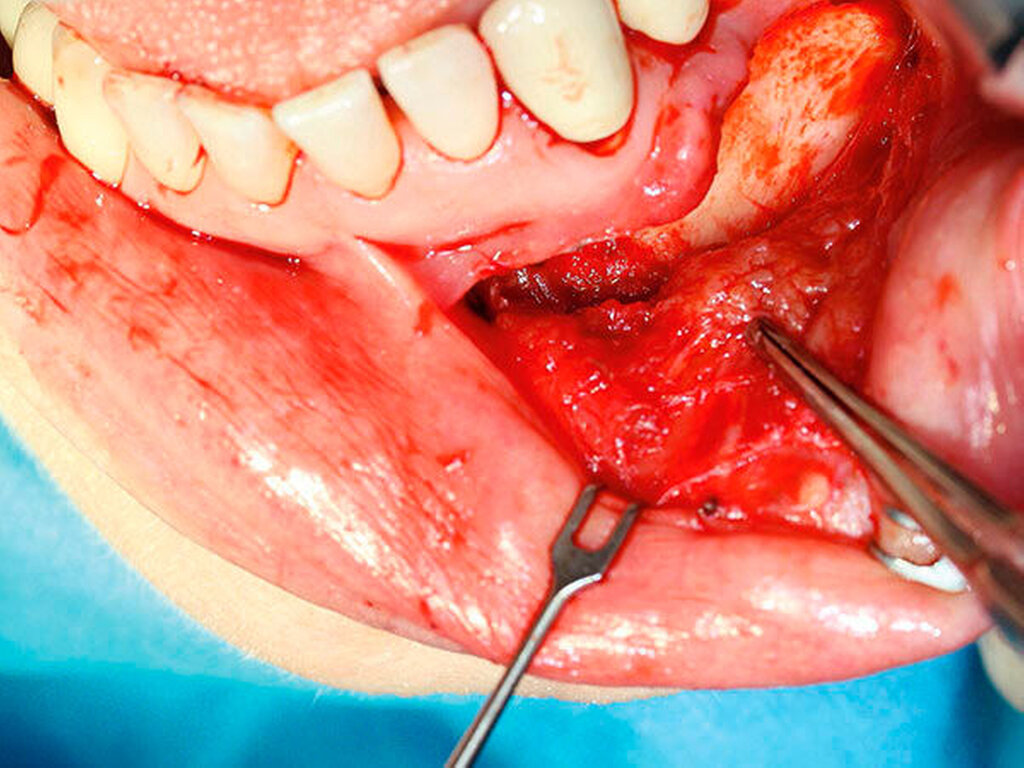

Diese wurde über einen intraoralen Zugang mit einer paramarginalen Schnittführung regio 32–35 durchgeführt. Nach Detektion und Sicherung des Nervus mentalis sowie Inzision des Periosts erfolgte die Darstellung und Präparation der knotigen Raumforderung (Abbildung 3).

Diese stellte sich gelb-gräulich dar und ließ sich vom Gewebe nur schwer abgrenzen. Daraufhin erfolgten die Resektion (Abbildung 4) unter Facialismonitoring sowie die primär plastische Rekonstruktion.